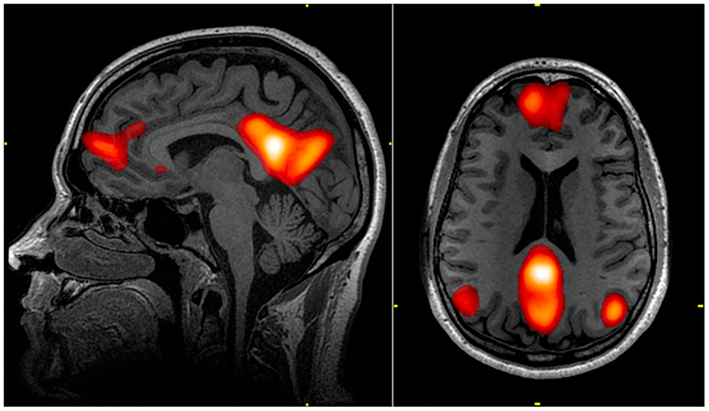

우리 뇌에는 디폴트 모드 네트워크(default mode network), 즉 DMN이라는 것이 존재한다.

디폴트 모드니까 멍때릴 때는 켜지고 업무나 운동 등 외부에 몰입거리가 있을 때는 꺼진다.

DMN이 켜져있을 때 우리의 뇌는 자신에 대한 생각으로 넘쳐나고 자아에 대한 의식들을 확립하게 된다.

하지만 과도하게 기능하면 내면에 지나치게 침잠해 자기 생각밖에 할 수 없는 상태가 되어버린다.

타인과의 소통능력, 일에 대한 집중도 역시 떨어지게 된다.

주요 우울장애가 있던 환자들의 경우 저 DMN이 과도하게 활성화 되어있었다고 한다.